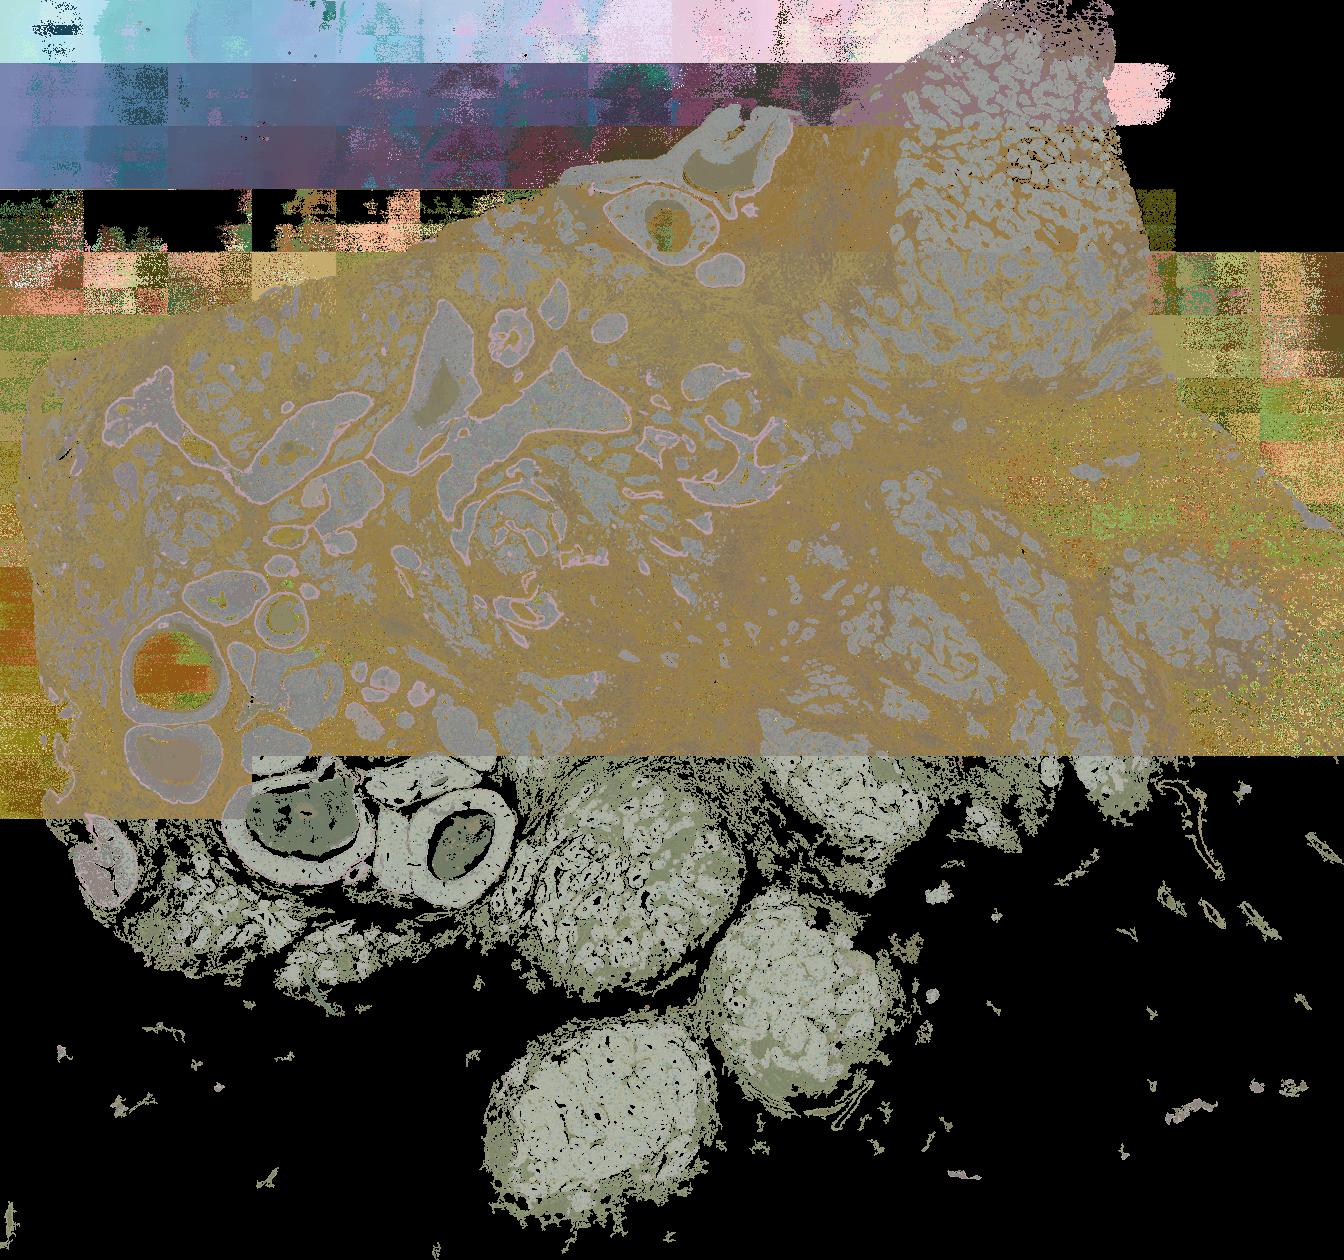

To study the spatial interactions among cancer and non-cancer cells1, we here examined a cohort of 131 tumour sections from 78 cases across 6 cancer types by Visium spatial transcriptomics (ST). This was combined with 48 matched single-nucleus RNA sequencing samples and 22 matched co-detection by indexing (CODEX) samples. To describe tumour structures and habitats, we defined ‘tumour microregions’ as spatially distinct cancer cell clusters separated by stromal components. They varied in size and density among cancer types, with the largest microregions observed in metastatic samples. We further grouped microregions with shared genetic alterations into ‘spatial subclones’. Thirty five tumour sections exhibited subclonal structures. Spatial subclones with distinct copy number variations and mutations displayed differential oncogenic activities. We identified increased metabolic activity at the centre and increased antigen presentation along the leading edges of microregions. We also observed variable T cell infiltrations within microregions and macrophages predominantly residing at tumour boundaries. We reconstructed 3D tumour structures by co-registering 48 serial ST sections from 16 samples, which provided insights into the spatial organization and heterogeneity of tumours. Additionally, using an unsupervised deep-learning algorithm and integrating ST and CODEX data, we identified both immune hot and cold neighbourhoods and enhanced immune exhaustion markers surrounding the 3D subclones. These findings contribute to the understanding of spatial tumour evolution through interactions with the local microenvironment in 2D and 3D space, providing valuable insights into tumour biology.